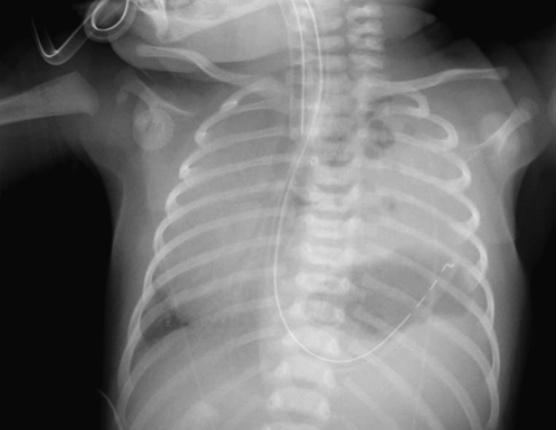

Diaphragmatic Hernia

path: failure of septum transversum to completely divide the pleural and coelomic cavities during fetal development. Herniation of intra-abdominal contents occurs during a critical period of lung development when the

pulmonary arteries and bronchi are branching. Pulmonary hypoplasia results from decreased pulmonary mass and bronchiolar branching as well as dysfunctional surfactant production.

PE: scaphoid abdomen

Diagnosis:

prenatal US

xray:

Associations